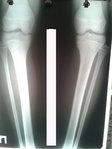

Рентген на фиксации.